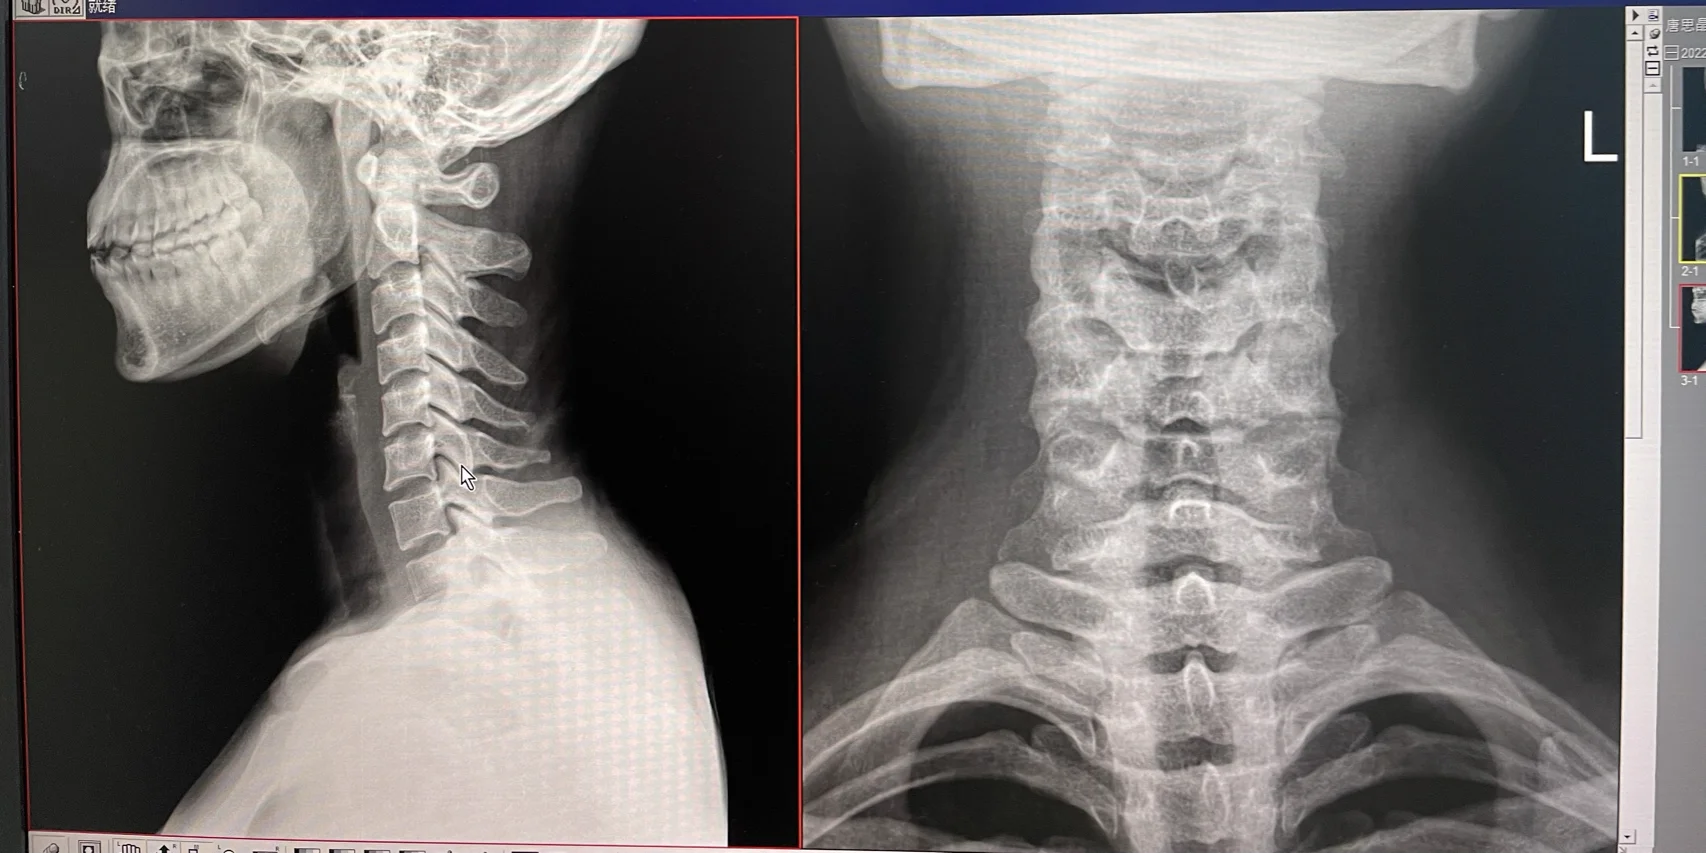

颈椎反弓能矫正颈椎正常情况下具有向前凸出的生理曲度,当这一曲度发生改变,向后凸出即形成颈椎反弓虽然矫正存在一定难度,但通过科学合理的方法,多数患者的症状和颈椎曲度能够得到改善矫正方法主要包括以下四类一改变生活习惯需时刻保持正确姿势,站立或坐立时挺胸抬头眼睛平视,避免低头或头部前倾。

颈椎反弓可以治好具体的治疗方法依据患者的年龄和引起颈椎反弓的原因而有所不同,主要包括以下几种情况青少年颈椎反弓原因通常由于长时间低头学习或做作业导致治疗方法通过适度的功能锻炼,如打羽毛球放风筝等,颈椎曲度可以慢慢地自行矫正中老年颈椎反弓状态颈椎反弓提示颈椎处在不健康的;颈椎反弓能否恢复需综合判断,部分患者可改善症状或恢复曲度,但恢复程度因人而异其核心影响因素包括反弓程度病因年龄及健康状况,具体恢复情况需结合个体差异与治疗措施综合评估儿童与青少年恢复概率较高因骨骼和肌肉处于发育期,若反弓程度较轻且由姿势不良等可逆因素导致,通过及时纠正不良习惯如。

颈椎反弓能否恢复正常需分情况讨论,轻症可能改善,重症难以完全恢复具体分析如下轻症患者通过综合干预可改善症状对于反弓程度较轻无神经压迫症状的患者,物理治疗如颈部按摩热敷低强度颈部运动可缓解肌肉紧张,改善局部血液循环药物治疗非甾体抗炎药肌松剂能减轻疼痛和炎症反应牵引;出现这种情况且颈椎反弓程度比较重,即使经过治疗后也不能够恢复,而且患者出现颈椎曲度反弓后容易患有颈椎病患者会出现上肢的皮肤感觉麻木疼痛肌肉力量减弱,出现手指灵活性障碍或者行走困难眩晕恶心等临床表现多数治疗以保守治疗为主,需要患者减少活动卧床休息,颈部可以给予针刺艾灸等方法。